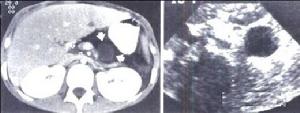

在腹部平片上可見囊壁鈣化影,其形態為圓形或月牙狀Warshaw報導67例胰腺囊腫病人,其中7例有鈣化影者均為胰腺囊腺癌,而胰腺假性囊腫、瀦留性囊腫和囊腺瘤病人多無鈣化灶。

可以顯示腫瘤的部位、大小及其與周圍器官之間的關係,有助於明確胰腺腫塊的囊、實性,囊腔的大小和多寡,囊內容物、囊壁及其間隔等的結構和形態的特徵,為診斷與鑑別診斷提供重要依據。